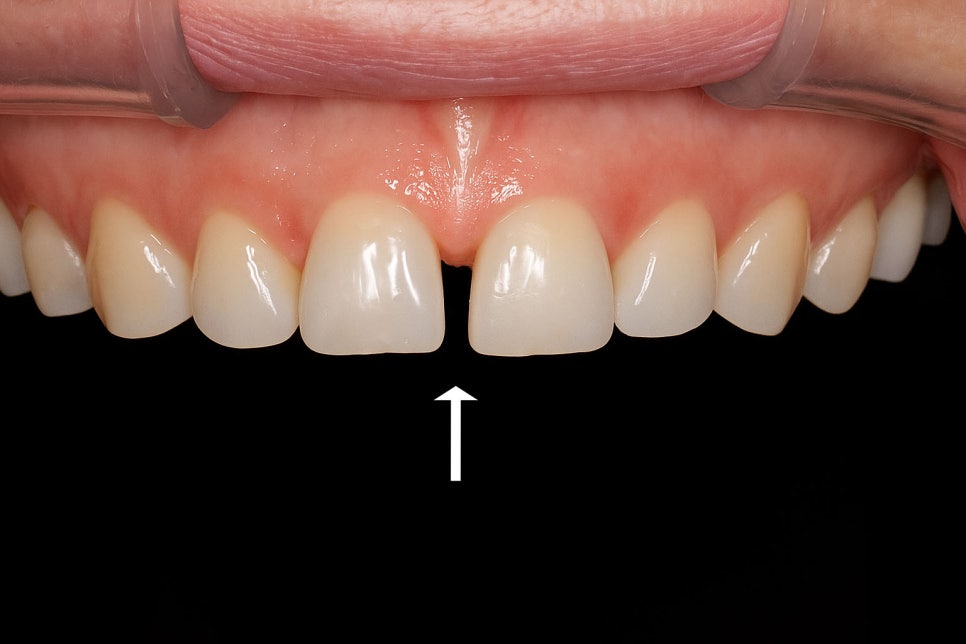

치아 사이가 벌어져 있는 것을

다이아스테마라 부르며

이는 특히 위턱의 정중앙 앞니 사이에서

자주 볼 수 있습니다.

선천적으로 생길 수도 있고

나이가 들면서 치주가 약해지면서 생기기도 합니다.

이런 공간이 있으면 발음을

제대로 하기 어려울 수 있으며

무엇보다 외모에 고민이 있을 거라 생각됩니다.

이때 치아를 깎지 않고 벌어진 사이 공간을 수복해

접촉점을 회복시켜볼 수 있습니다.

다만 벌어진 정도가 심하거나 잇몸 질환

및 심한 부정교합이 같이 있다면

다른 방법을 고려해야 될 수도 있습니다.

따라서 당산동 치과 는 의료진과의 진단이

선행되어야 됨을 말씀드립니다.